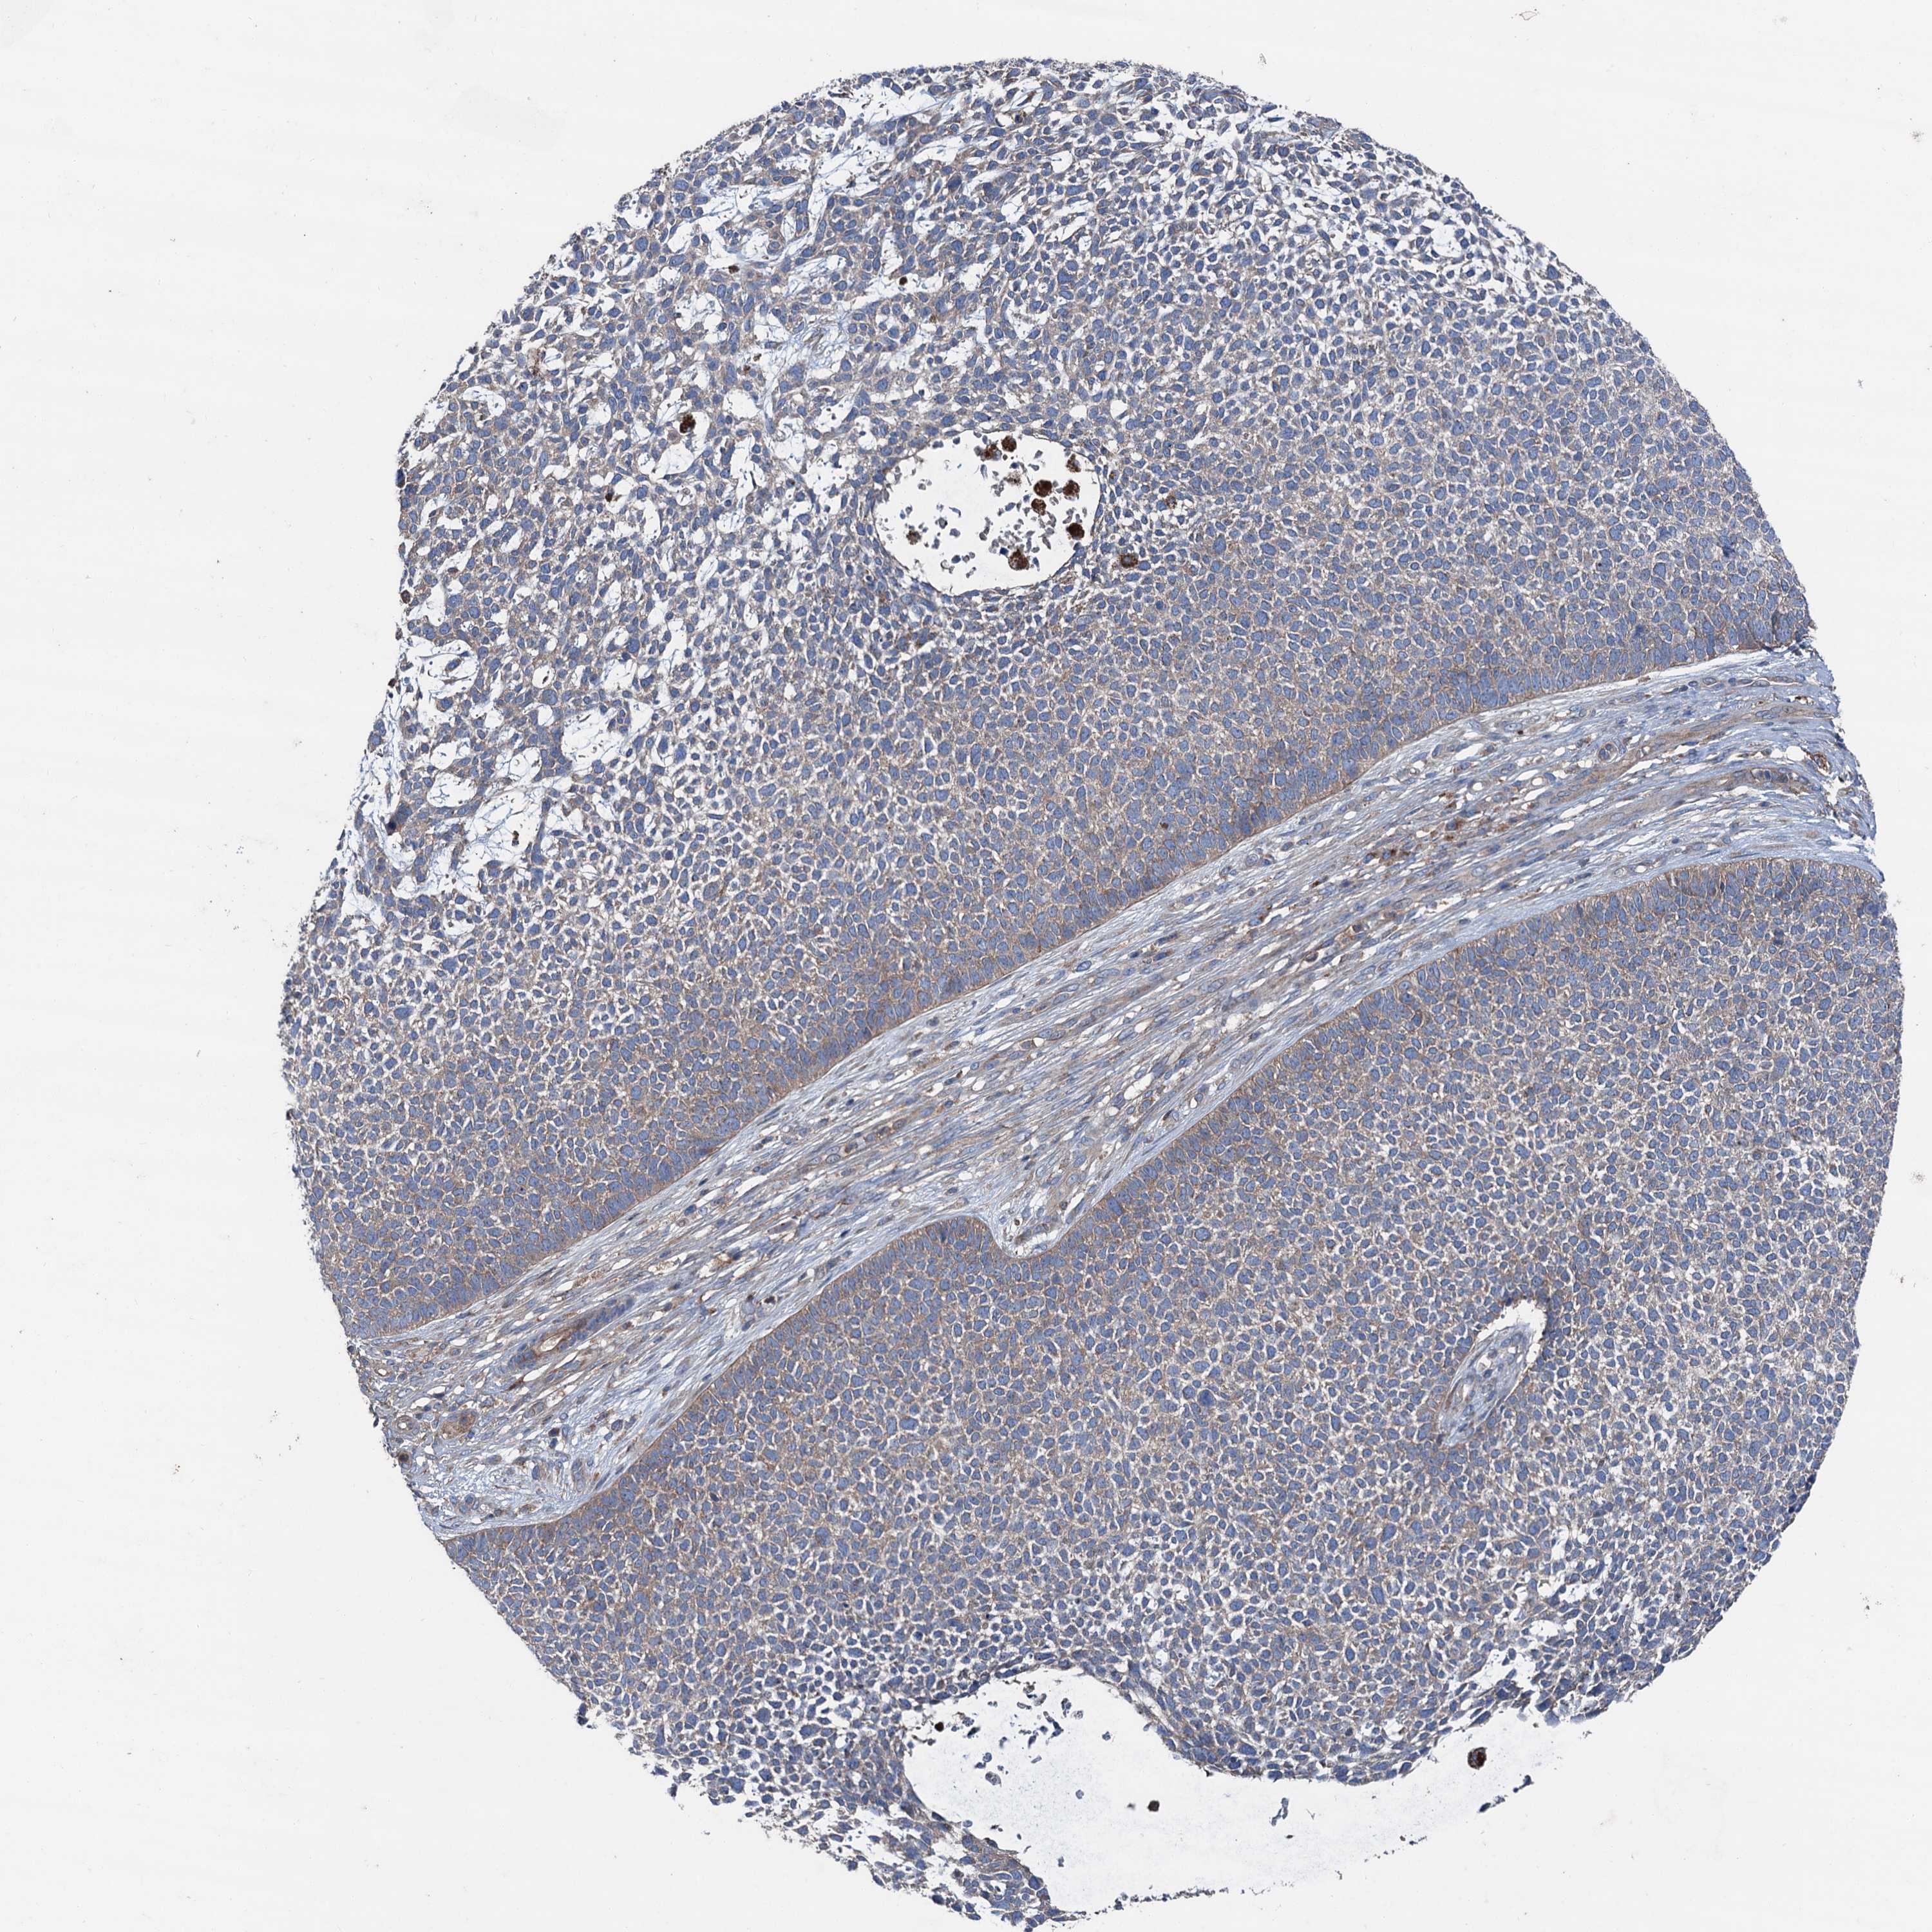

SKIN CANCER - Protein expressioni

A mouse-over function shows sample information and annotation data. Click on an image to view it in a full screen mode. Samples can be filtered based on level of antibody staining by selecting one or several of the following categories: high, medium, low and not detected. The assay and annotation is described here.

Antibody stainingi

Antibody staining in the annotated cell types in the current human tissue is reported as not detected, low, medium, or high, based on conventional immunohistochemistry profiling in selected tissues. This score is based on the combination of the staining intensity and fraction of stained cells.

Each image is clickable and will lead to virtual microscopy that enables deeper exploration of all samples and also displays staining intensity scores, fraction scores and subcellular localization as well as patient and tissue information for each sample.

Antibody HPA038804

Squamous cell carcinoma, NOS